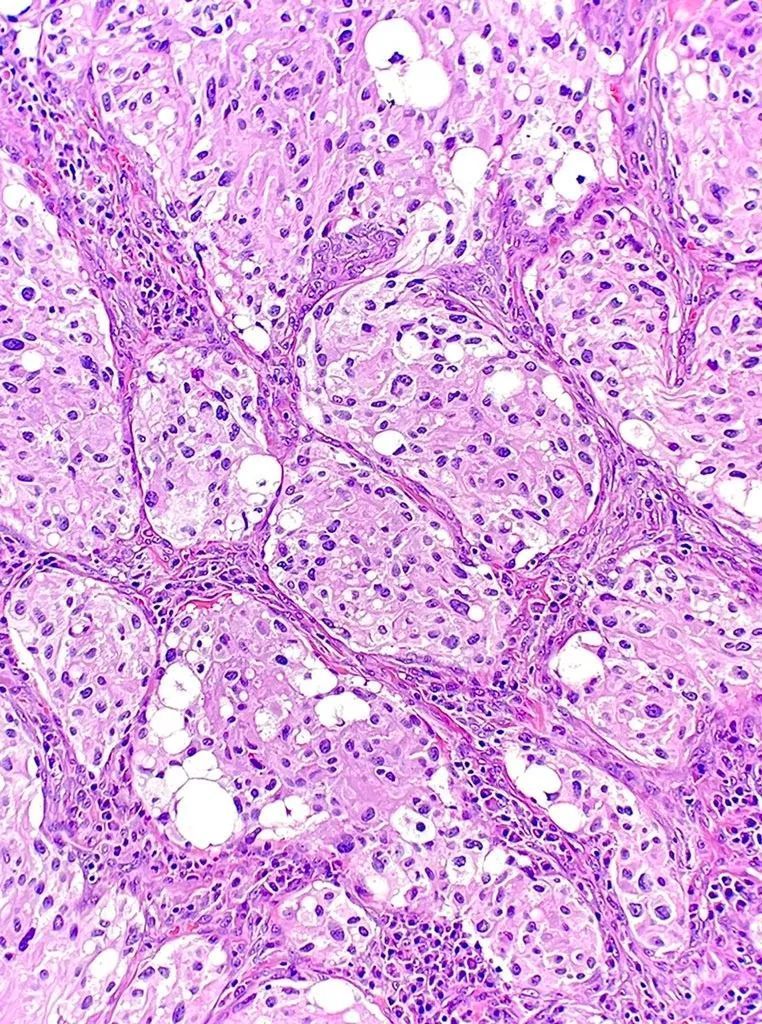

Happy Monday everyone! This is an incidental finding in a reduction mammoplasty. What is your diagnosis? #breastpath #PathTwitter WashU Medicine Pathology & Immunology WashU Medicine Pathology & Immunology Education